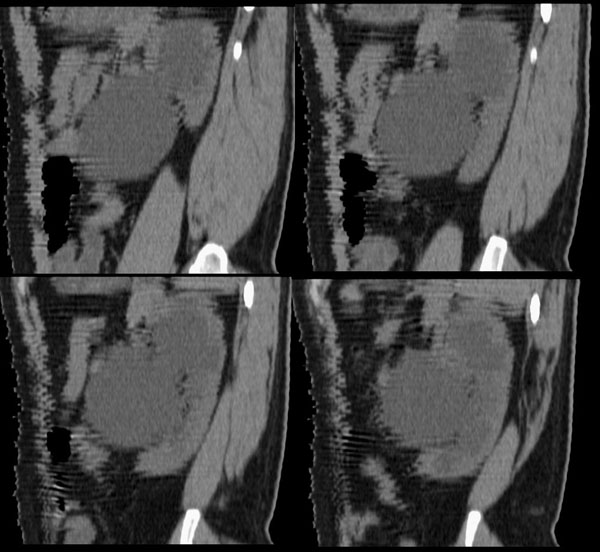

左侧输尿管冠、矢状重建:

左侧肾盂、肾盏扩张,肾盂输尿管移行部突然狭窄,未见明显占位及高密度结石影,体检发现,考虑:先天性肾盂输尿管移行部狭窄。(原因多方面,有先天缺陷造成移行部结构异常或因为迷走血管、纤维索条引起肾盂输尿管的压迫扭曲所致。)大剂量ivp或肾盂造影有助于显示输尿管狭窄部位及形态。